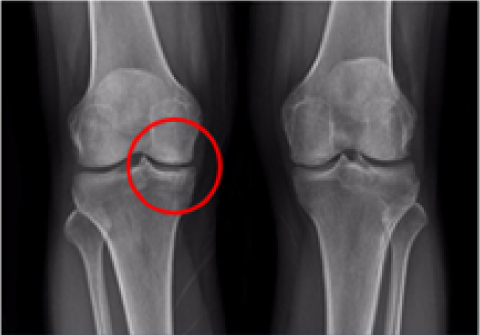

무릎 인공관절 부분치환술

2016.06.27

2016.12.28